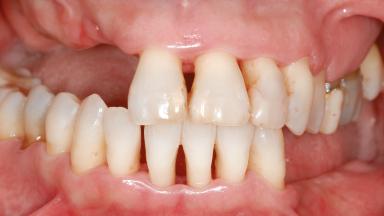

Shell Technique for Horizontal and Vertical Maxillary Bone Augmentation in a Partially Edentulous Patient with Aggressive Periodontal Disease

A 46-year-old woman was referred for treatment whose main complaints were mobility of her fixed partial dentures (right maxilla and left mandible) and periodontal bleeding during function. She also reported having taken systemic antibiotics to treat recurrent swelling in the area of the upper left molars. The patient had not seen a dentist for at least 2 years. She did not smoke and had no history of major systemic disease other than two minor orthopedic procedures some years back. The first-visit examination revealed poor plaque control, tooth mobility, periodontal disease, and a residual dentition widely associated with deep periodontal pockets.

Prosthesis Type FDP

Defining Characteristics Up to three missing teeth to be replaced with an implant-borne restoration or restorations

Occlusion/Articulation Irregular with no need for correction